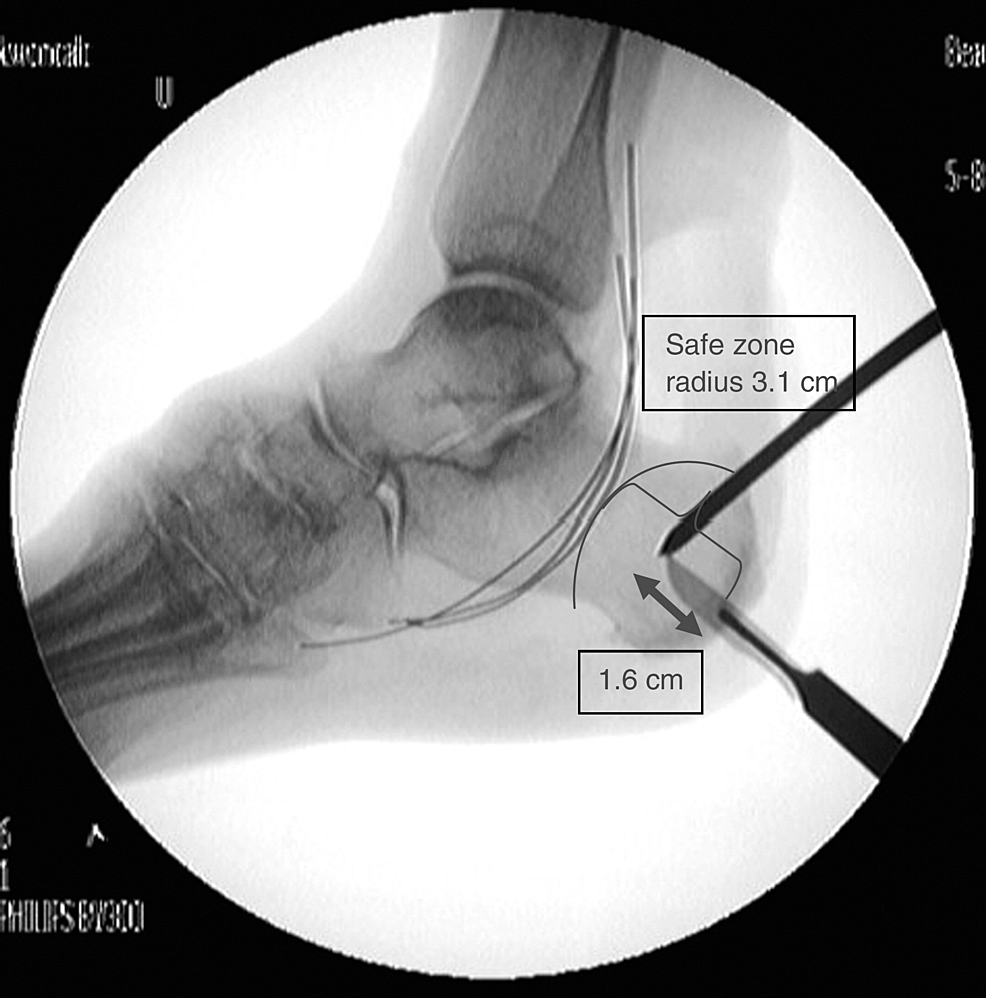

Defining an Anatomic and Radiographic Safe Zone for Posterior Malleolar Anatomic Safe Zone we found the anatomic safe zone to be well defined using the bicipital tuberosity view and reproducible using bony anatomic landmarks (ie, radial styloid and lister tubercle). an understanding of these data and their consistency will help to establish arthroscopic safe zones for the. the purpose of this study was to identify a safe zone for cerclage. Anatomic Safe Zone.

Cureus Addition of a Second Calcaneal Pin for Spanning Ankle External Anatomic Safe Zone the purpose of this study was to identify a safe zone for cerclage passage referencing reliable superficial anatomical. we found the anatomic safe zone to be well defined using the bicipital tuberosity view and reproducible using bony anatomic landmarks (ie, radial styloid and lister tubercle). 97 was conducted with the goal of determining an anatomic safe zone. Anatomic Safe Zone.

An Anatomic Safe Zone for Posterior Ankle Arthroscopy A Cadaver Study Anatomic Safe Zone the purpose of this study was to identify a safe zone for cerclage passage referencing reliable superficial anatomical. the purpose of this study was to identify a safe zone for cerclage passage referencing reliable superficial anatomical. this chapter is intended to give an overview of anatomic safe zones so these principles and components can be. an. Anatomic Safe Zone.

An Anatomic Safe Zone for Posterior Ankle Arthroscopy A Cadaver Study Anatomic Safe Zone the purpose of this study was to identify a safe zone for cerclage passage referencing reliable superficial anatomical. this chapter is intended to give an overview of anatomic safe zones so these principles and components can be. we found the anatomic safe zone to be well defined using the bicipital tuberosity view and reproducible using bony anatomic. Anatomic Safe Zone.

An Anatomic Safe Zone for Posterior Ankle Arthroscopy A Cadaver Study Anatomic Safe Zone the purpose of this study was to identify a safe zone for cerclage passage referencing reliable superficial anatomical. an understanding of these data and their consistency will help to establish arthroscopic safe zones for the. an anatomic safe zone was characterized by measuring distances from both the upper and lower subscapularis nerve insertions with. 97 was. Anatomic Safe Zone.